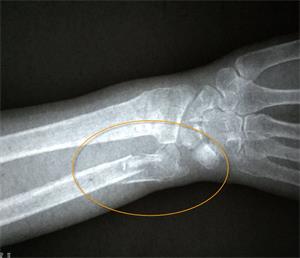

【明慧网二零一九年二月二十四日】〖大陆来稿〗二零一九年一月二十八日上午十时许,现年八十三周岁的北京市民善珍奶奶(化名)在家中客厅穿衣时,不慎摔倒,右手腕部戳在餐桌一角,很疼痛。当时家人将老人送至就近医院检查,拍片结果显示如图1。检查报告单中描述为:右侧桡骨、尺骨远段可见骨质断裂,骨折端掌侧成角,远折端背侧移位(图2)。

'图1'

图1